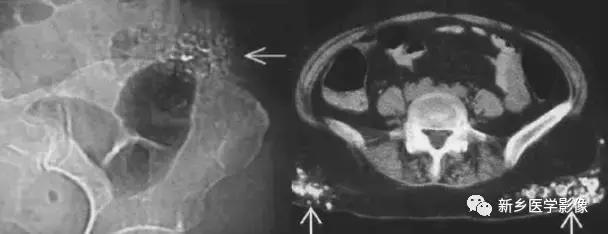

子宫平滑肌瘤(纤维瘤)

主要位于盆腔内,表现为不均一的点状钙化

卵巢肿瘤畸胎瘤

常见的为畸胎瘤以及合并钙化的卵巢癌